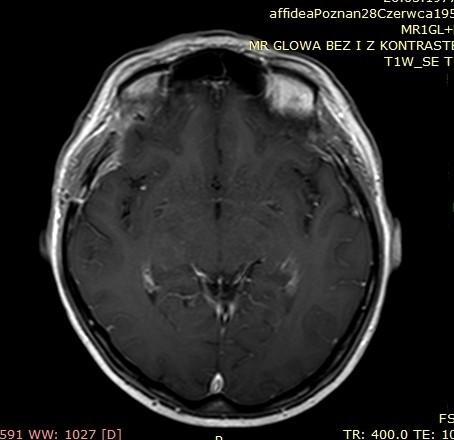

OPONIAKI DUŻYCH ROZMIARÓW I OPONIAKI OLBRZYMIE

Od wielu lat zajmuję się chirurgią oponiaków wewnątrzczaszkowych o różnych lokalizacjach oraz rozmiarach. W grupie operowanych przypadków znalazły się także oponiaki dużych rozmiarów i oponiaki olbrzymie. Guzy te potrafią rosnąć powoli. Wielokrotnie objawy kliniczne przez wiele lat są niespecyficzne - tylko bóle głowy!!! Początkiem przyspieszonej diagnostyki bywa pierwszy w życiu napad padaczkowy. Tak było w grupie prezentowanych przypadków dużych/olbrzymich oponiaków. Wiele z tych guzów pomimo swojej naturalnej łagodności stanowi poważne wyzwanie operacyjne. Operacja oponiaka – to działanie operacyjne wobec guza rosnącego zewnątrzmózgowo, wielogodzinne spokojne oddzielanie i usuwanie „żeby mózg o tym nie wiedział”

Poniżej przedstawiono grupę operowanych pacjentów.

Pacjent pierwszy - Guz usunięty całkowicie, guz łagodny. Pacjent w stanie dobrym, bez objawów neurologicznych – wypisany do domu.

Przed operacją

Tak jak napisałem guzy - oponiaki potrafią rosnąć powoli nie dając żadnych objawów, mózg dostosowuje się do utraty rezerwy wewnątrzczaszkowej dlatego, że proces przebiega powoli. Początkowym objawem był pierwszy w życiu napad padaczkowy. Potem diagnostyka – rezonans magnetyczny i operacja oponiaka. Działanie operacyjne wobec guza rosnącego zewnątrzmózgowo, wielogodzinne spokojne oddzielanie i usuwanie „żeby mózg o tym nie wiedział”

Poniżej prezentacja badan diagnostycznych:

• Ryc 1-7 – badania diagnostyczne przedoperacyjne,

• Ryc 8-13 – badania po operacji.

Pacjentka przyjęta nieprzytomna po napadzie padaczkowym – podczas operacji guz został usunięty całkowicie, miał charakter łagodny. Pacjentka w stanie dobrym, bez objawów neurologicznych – wypisana do domu.